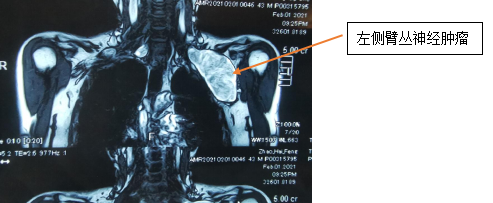

陈主任先安排患者进行相关检查,从体格检查、颈胸部增强CT、超声及磁共振结果来看,考虑患者左、右侧锁骨下肿物的性质为神经源性肿瘤——神经鞘瘤的可能性大。且目前左侧肿瘤已压迫胸腔,锁骨下良性肿瘤多数为神经源性肿瘤,特殊性在于肿瘤位于锁骨下,起源于臂丛神经,与锁骨下动静脉伴行。

2月4日,手外三团队进行术前讨论,一致认为患者右侧肿物较左侧小,患者右侧肿瘤未影响患肢活动,予左侧臂丛神经肿瘤切除,术后颈部空腔较大,出现皮下淤血,可导致呼吸困难、窒息可能,且肿瘤已压迫胸腔,稍有不慎胸膜破裂,有血气胸形成可能,手术风险较大。由于锁骨下方解剖困难,多数需要切断锁骨,切断锁骨还需内固定,二期再手术取出内固定,对患者造成较大损伤,因此陈主任手术团队制定出另一套损伤小、恢复快的方案——不切断锁骨,直接采取“锁骨上、下联合切口”,通过锁骨上、下切口于锁骨下做通道取出肿物手术方案。

次日,手术按时进行,术中探查见肿物与臂丛神经相连,上肢的一些主要的动、静脉都在肿物的下方。手术风险性非常大,稍有不慎,就会损伤血管造成大出血的状况,且难以修补。术中按照术前拟定的手术方案,采取锁骨上、下切口,通过锁骨下隧道方式仔细剥离肿物上神经束,术中见神经瘤与神经粘连严重,予以松解,于锁骨上下切口内采取“会师法”将神经瘤完全剥离。经过4个小时的努力,手术顺利完成。取出的肿物经过测量,大小约12cm×6cm×5cm,竟然比一个拳头还要大。